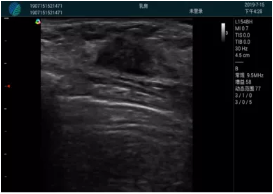

可視化穿刺引導

M20實時引導:向包塊后方間隙注射利多卡因

清晰顯示腺體內低回聲快影,邊界清晰,包膜較光滑

確定進針路徑并實時監(jiān)測抽吸針與腫塊位置關系

抽吸針進入腫塊內部進行旋切

抽吸過程中可見腫塊明顯縮小,并根據腫塊位置改變針道位置

抽吸旋切后再進行超聲復查,原腫塊區(qū)域未見殘留組織及出血

超聲引導下抽吸旋切取出的腫塊組織